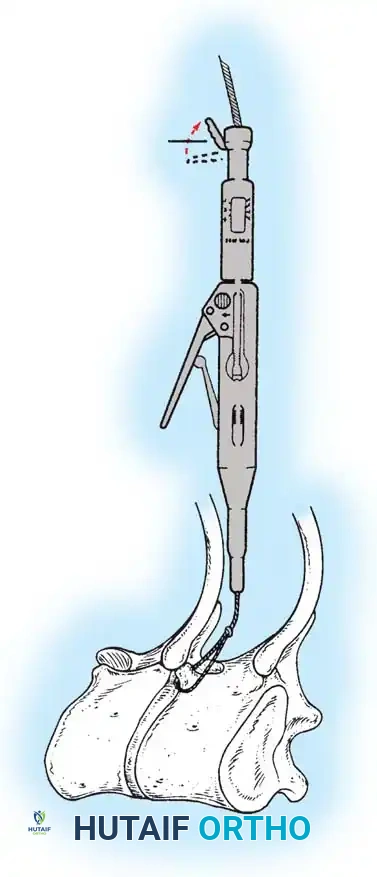

Fig. 38-26: The Moe technique of thoracic facet fusion, demonstrating the creation of hinged bone flaps.

- Expose the spine fully to the tips of the transverse processes.

- Using a sharp osteotome or Cobb gouge, begin a cut over the cephalad articular process at the base of the lamina.

- Carry this cut along the transverse process almost to its tip. Bend this cortical fragment laterally so it lies between the transverse processes, ideally leaving it hinged on its lateral periosteal attachment to preserve local vascularity.

- Thoroughly denude all articular cartilage from the superior articular process using a sharp curet.

- Make a secondary cut in the superior articular facet, working medially to laterally, producing another hinged fragment.

- Pack the resulting intra-articular defect tightly with cancellous bone graft.